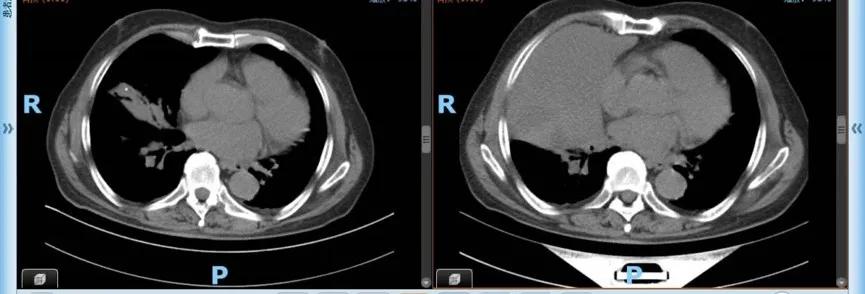

根据浙江医院老年肿瘤诊治的特色和优势,张宇按规范为陈大伯做了治疗前的全面评估— 老年肿瘤评估 ,随后根据结果,组织了 多学科诊治大讨论 ,综合考虑病情、年龄、身体状况及基础疾病等因素,同时也考虑到陈大伯对生活质量的要求,为他制定“个体化”的肺癌治疗方案,最终选择最新的 免疫治疗联合单药化疗 的方式,经过 3个周期 的阶段治疗,评估后显示目前的治疗取得了非常好的疗效。肺部的病灶明显缩小,除了有一些皮疹,日常生活没有受到明显影响。“我们会继续规范和有针对性地为他提供医疗服务,非常期待下一步的疗效。”张宇说。

治疗后(左图)及治疗前(右图)

当张宇告诉陈大伯肿瘤缩小了一大半时,大伯悬着的心也放下来。“现在我治疗间歇期,在家里照样能干家务,出去和邻居唠家常,还能干轻一些的农活,我对治疗结果非常满意,感谢浙江医院的张主任和他的团队,为我又带来了希望!”陈大伯感激道。